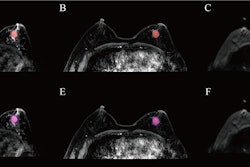

Abbreviated axial MRI images show a 7-mm irregular mass with irregular margin (arrows) in the right upper inner quadrant with early rapid enhancement (BIRADS 4). The participant was recalled and underwent an MRI-guided vacuum-assisted biopsy that showed sclerosing adenosis with microcalcifications and usual ductal hyperplasia and focal apocrine metaplasia. On the full-protocol images (not shown), the lesion was T2-weighted hypointense and showed diffusion restriction and washout kinetics in the delayed phase, characteristics that would not have reversed the decision to recall the participant.RSNA